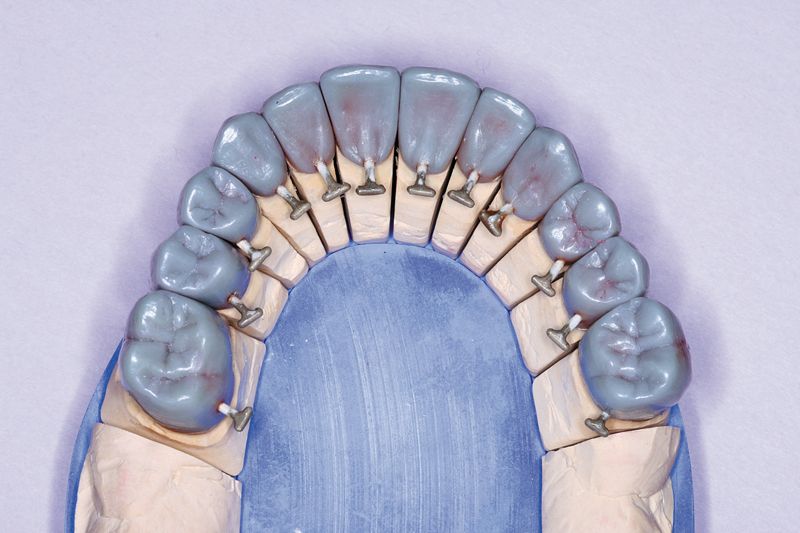

09 The patient had lost a significant amount of soft and hard tissue in the maxillary arch. To recreate the missing soft-tissue volume, the BellaTek Copy-Mill Framework was masked with an opaque, and zirconium silicate microceramic material (Ceramage, Shofu) was applied (Figs. 9 and 10). This material is available in an assortment of gingival colors that correspond to color variations in the natural dentition. The gingival mask was finished with standard abrasives such as stones and rubber wheels and polished.

Fig. 9?Facial view of the gingival microceramic material on the framework.

Fig. 10?Lateral view of the gingival microceramic material on the framework.

Fig. 11?Full contour wax patterns seated on the BellaTek Framework.

10 The copy-milled framework was duplicated, using a silicone-duplicating material that was mixed, poured into a duplicating flask, and put under pressure at 4 bars for 40 minutes. The model was removed from the silicone, and a new master cast was fabricated in die stone. Individual full-contour wax patterns were cast in Galileo (Jensen) (Fig. 11). These were finished, put back on the individual dies (Fig. 12), and the full contours of the teeth were re-established in wax. This set of wax patterns was then invested, and a pressable ceramic porcelain system was used to fabricate the all-ceramic crowns (Authentic, Jensen).

Fig. 12?Full contour was patterns on the individual dies.

Fig. 13?The crown restorations in place on the BellaTek® Copy-Milled Framework.